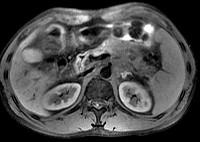

问题 男45岁、腹部胀痛不适、胃纳减退、体重减轻、中腹部可触肿块,影像检查如图,应诊断为()

选项 A.急性胰腺炎 B.慢性胰腺炎 C.胰腺体尾部癌 D.胰岛细胞瘤 E.腹膜后淋巴结结核

答案 C